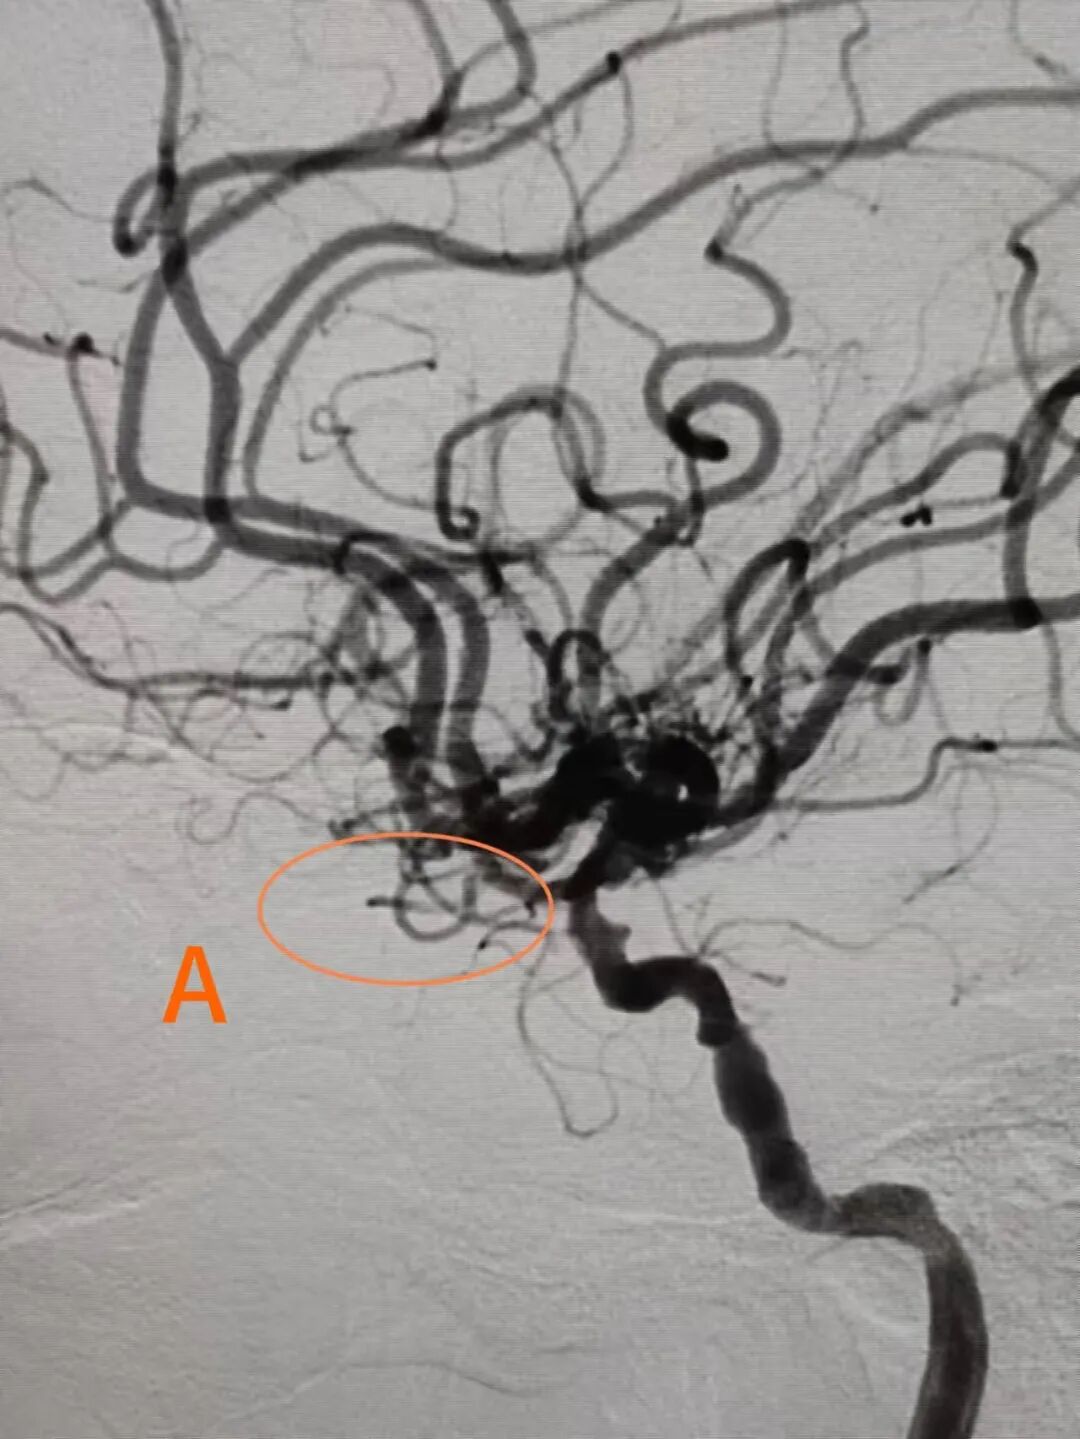

神经内科专家团队为郑叔紧急开通了绿色通道,并根据其病情,制定了个体化的溶栓治疗方案,随即实施了急诊手术。术程30分钟的紧急溶栓,使郑叔受阻的中央动脉很快恢复畅通,经血管造影显示该血管循环供血良好。

溶栓前未见眼动脉显影